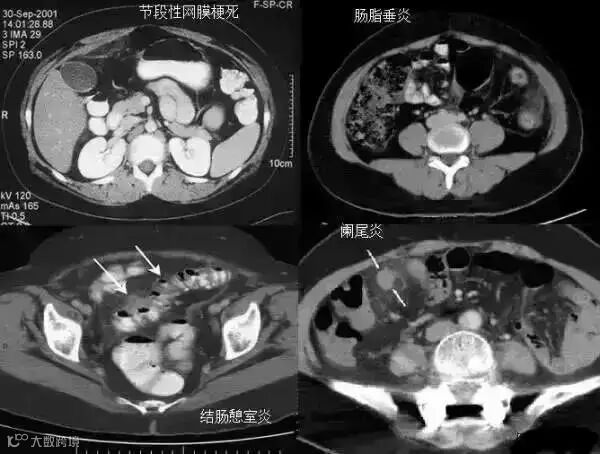

3不成比例脂肪绞缠征

不成比例脂肪绞缠主要指的是增厚肠壁和周围脂肪在数量方面比例的严重失衡。在少数急性胃肠道疾病中,以肠壁相邻的肠系膜为中心而不是以肠壁为中心,因此肠壁周围脂肪增厚明显高于肠壁厚度。和这一征像相关的疾病主要包括4类:憩室炎、肠脂垂炎、网膜梗死和阑尾炎。胃肠道的大多数炎性疾病包括感染性的、非感染性的和局部缺血性的病变,都是以肠道为中心。这些疾病的肠壁增厚程度往往超过相邻脂肪条索的厚度。但是对于少数以肠壁临近系膜为中心的疾病,脂肪增生明显超过肠壁的厚度。

左上图:右侧腹横肌深面、胆囊内前方梭形囊性病变,有壁但不均匀,略有强化。与腹横肌成锐角,腹横肌肥厚。周围脂肪模糊,有索条点状影。

右上图:邻近降结肠远端系膜壁旁可见一卵圆形类似脂肪密度的病变,周边可见火焰样炎性改变,邻近肠壁有轻微增厚,无明显脓肿及肠梗阻征象。

左下图:肠壁增厚,结肠袋襞显影不良,以及结肠周围脂肪束条状改变。

右下图:CT显示壁明显增强的管状结构(箭头),右中腹的脂肪系膜反应。